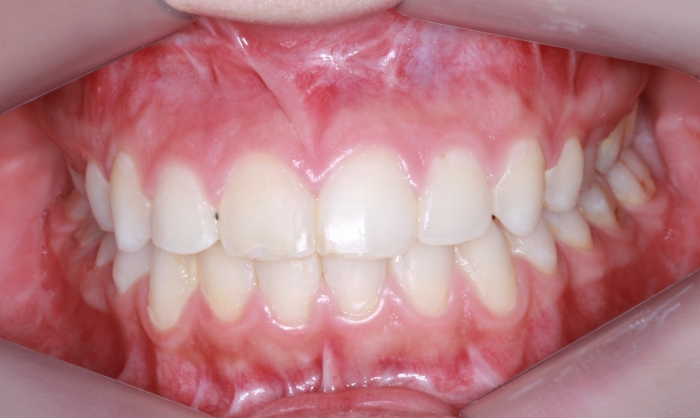

Mordida inicial